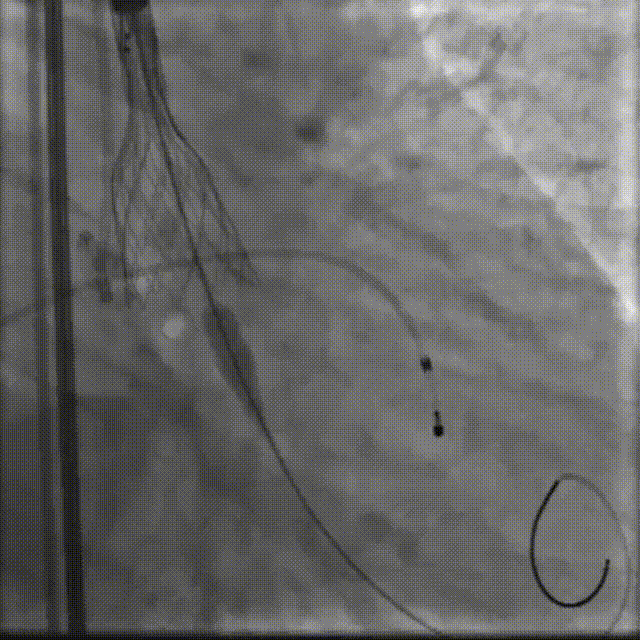

手术影像

主动脉根部造影

18mm球囊预扩

球扩后瓣膜开始定位

工作位造影:位置理想

最终造影:位置理想,形态良好,无漏

撤出大鞘